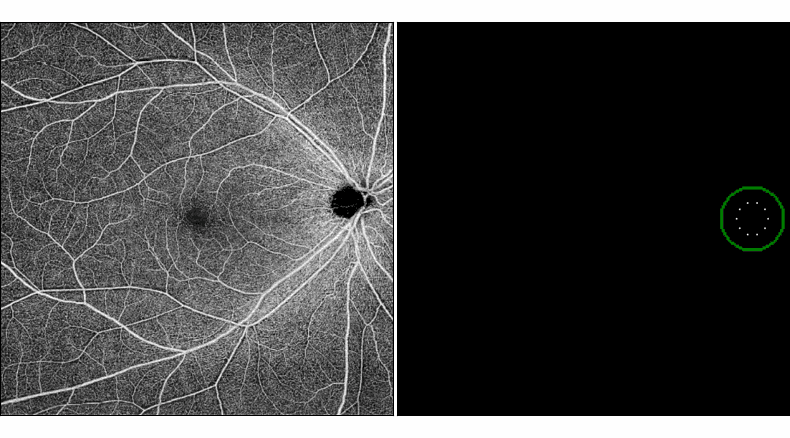

図 ヒト網膜の撮影画像 (左) と数理モデルによる再現 (右)

図2 光干渉断層血管撮影画像と数理モデル結果図の比較

(a): 光干渉断層血管撮影画像。(b): 数理モデル結果図。研究グループが構築した数理モデルは、①視神経円板から放射状に拡がる血管構造、②上下の耳側アーケード血管、③中心窩無血管域構造、④中心窩無血管域へ向かう求心的走行、⑤中心窩無血管域耳側で上下から対面し境界が形成されるような配列といった複数の構造的特徴を再現した。